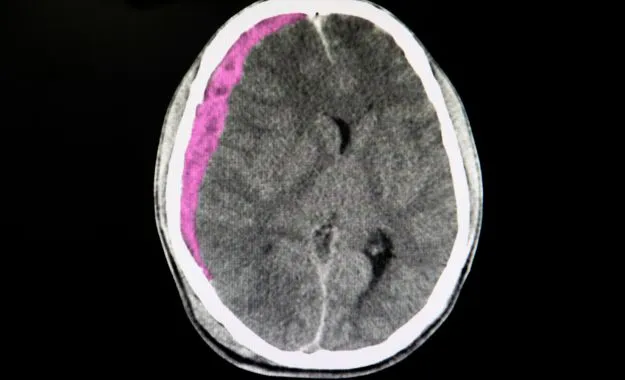

hématome sous dural

L'hématome sous-dural représente la complication la plus fréquente et la plus redoutable chez les seniors. Cette accumulation de sang entre le cerveau et la dure-mère peut se développer lentement, sur plusieurs jours ou semaines. Chez les personnes âgées, même un choc mineur peut provoquer cette lésion en raison de la fragilité accrue des vaisseaux sanguins et de l'atrophie cérébrale naturelle qui crée un espace plus important dans la boîte crânienne. Les symptômes peuvent inclure des maux de tête persistants, une somnolence progressive, des troubles de la mémoire ou des changements de comportement.